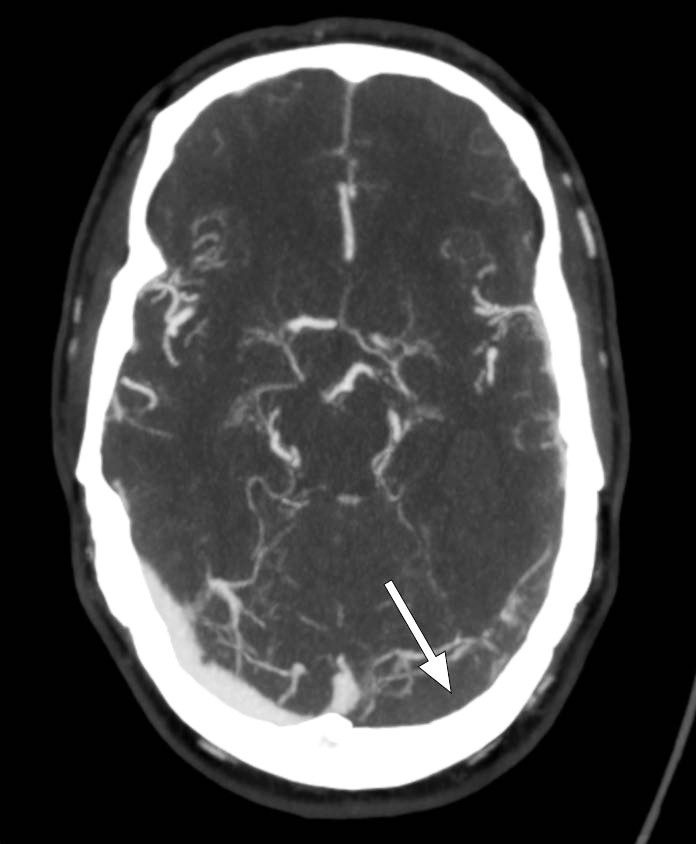

Ved innkomst fremsto han forvirret, søvnig og med afasi. CT caput avdekket intracerebral blødning i venstre temporallapp, og pasienten ble overflyttet til universitetssykehus for observasjon. Ved ankomst der var pasienten våken, men desorientert og hadde afasi uten andre fokalnevrologiske utfall. Han skåret 4 poeng på National Institutes of Health Stroke Scale, forenlig med et mindre hjerneslag. Kontroll-CT caput uten kontrast viste uendret størrelse av hjerneblødningen, og det ble reist mistanke om hemoragisk venøst infarkt grunnet tegn til cerebral venetrombose (figur 1). Supplerende CT-venografi viste manglende kontrastfylning av sinus transversus og sinus sigmoideus på venstre side, som bekreftet diagnosen (figur 2). Det ble samme dag startet behandling med lavmolekylært heparin i form av dalteparin 100 IE/kg to ganger daglig.